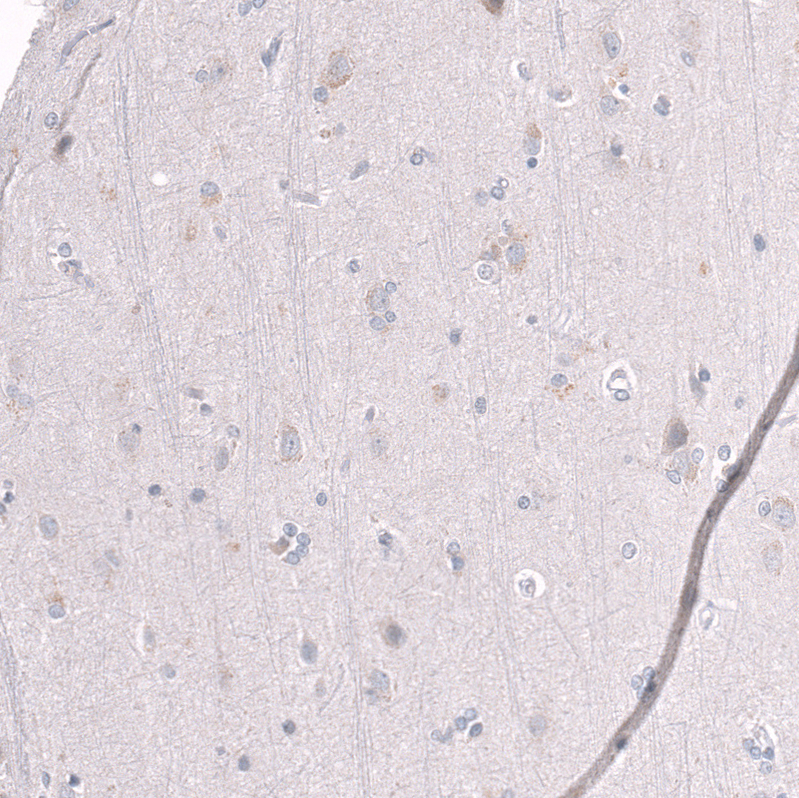

Immunohistochemistry analysis in human testis and cerebral cortex tissues using AMAb91750 antibody. Corresponding EZH2 RNA-seq data are presented for the same tissues.